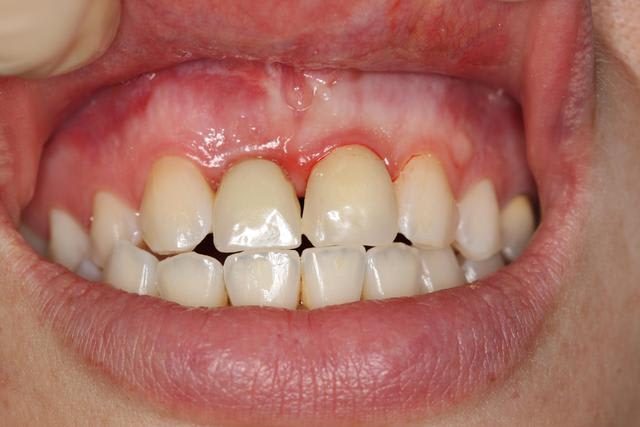

Provisoires

Gencive légèrement moins galbée sur implant

06/01/2012 à 01h42

joli...;-)

mais tu devrais un poil augmenter l'épaisseur au collet en épaississant le composite...çà va refouler ta gencive en vestibulaire et comme en même temps çà va la faire remonter un peu, tu auras les collets plus alignés...;-)

dommage en tout cas, ton implant, un tout petit peu plus enfoui et çà aurait été parfait...

+1 et élargi la face mésiale de 11 pour avoir un profil de la papille centrale plus symétrique